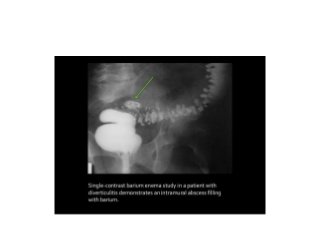

• Single-contrast barium

enema study

demonstrates

diverticulitis of the

descending colon with

fistula formation in the

small bowel.